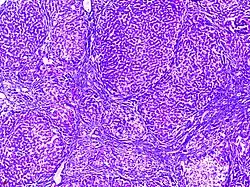

Dysgerminoma | Dysgerminoma characterized by uniform cells resembling primordial germ cells separated by fibrous septa with lymphocytes. | Category: Histopathology of ovarian dysgerminoma | Ovarian dysgerminoma |

![]() |